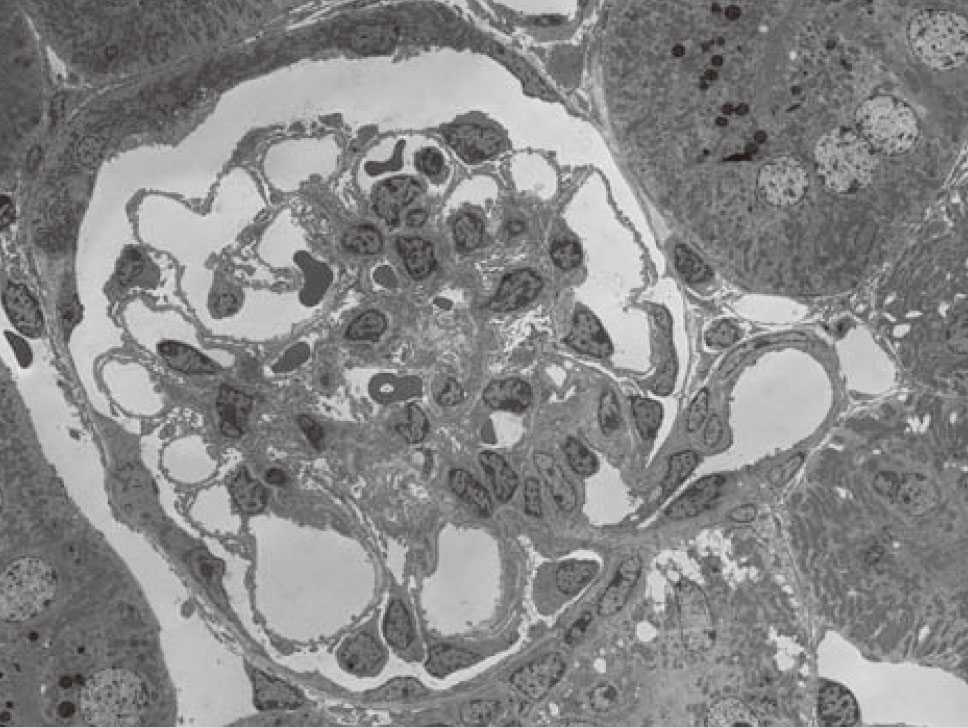

肾脏切片

加速电压:30kV

观察倍率:x1,300